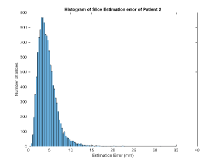

Exp. 2: Fetal brain data is used to test the robustness of our approach under real conditions. Fetuses younger than 30 weeks very often move a lot during examination. Fast MRI sequences allow artifact free acquisition of individual slices but motion between slices corrupts consistent 3D information. Fig. 3 shows that our method is able to accurately predict also under these conditions. For this experiment we use from three orthogonally overlapping stacks of ssFSE slices covering the fetal brain with approximately 20-30 slices each. We are ignoring the stack transformations relative to the scanner and treat each individually. For , 28 clinically approved motion compensated brain reconstructions are resampled into a volume with spacing. A density of 500 unique sampling normals has been chosen via the Fibonacci sphere sampling method with 25 sampling planes evenly spaced between -25 to +25 on the Z-axis. This gives a plane spacing of 2mm, sampling only the middle portion of the fetal brain. Training took approximately 10hrs for 30 epochs. Prediction, i.e., the forward pass through the network, takes approx. 12 ms/slice.

Here we show for Exp. 1, Exp. 2, and Exp. 3 randomly selected examples of images that have been presented to the network (ground truth) compared to an image sampled at the predicted location.

In these experiments, we present a ground truth (GT) image to the network to estimate the respective transformation parameters needed to reorient the slice in its correct world co-ordinates. Using the transformation parameters, we generated a slice from the 3D atlas in the location where the network has predicted that slice should be (denoted as SVRNet).

The slices are compared side-by-side to give a visual representation of “where the slice really is” and “where the network thinks the slice is”.

0..5.2 Exp. 2:

Slices, from a motion corrupted MRI stack, are segmented and cropped. Since there is no ground truth for the queried images, an arbitrary fetal atlas is used for visualization in Fig. 11 and 12.